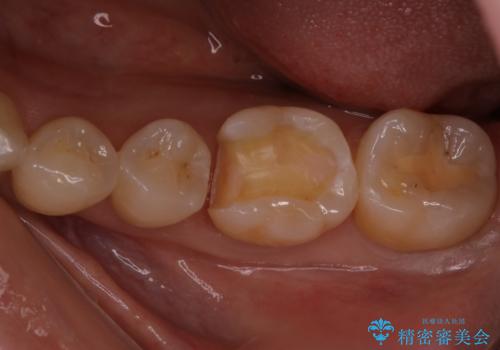

定期検診で虫歯発見。セラミック治療

- 定期検診に通われている患者様で虫歯を発見し患者様に話をしたら、治療を進めていきたいとのことだったので治療を行いました。

まずは虫歯をしっかりと取る事が大切です。

虫歯をとった後は、削った形に型を取る事で隙間なく歯にあった被せ物ができてきます。